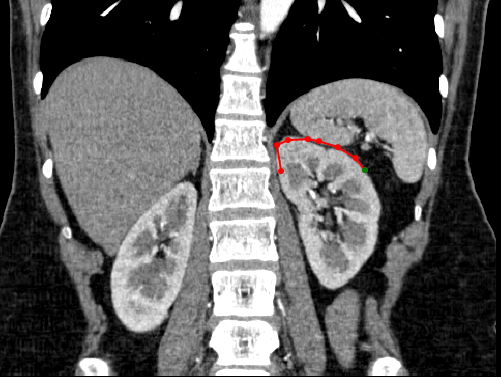

» Create curve- simple click on the starting position of interest and then continue to click along the path of interest. A continuous line will be created between each clicked point and a circle will be shown for each click that was conducted. To finish the curve, simple double click using the mouse.

» Adjust curve– To adjust the shape of the curve, simple select one of the points shown along the curve and drag it to the new position of interest